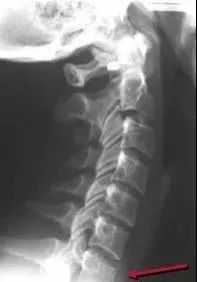

七、单纯型压缩性骨折

椎体变扁呈楔形,前缘塌陷>3mm,常累及椎体上终板。